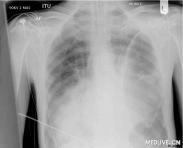

• 膿胸

病菌侵入胸膜腔,產(chǎn)生膿性滲出液積聚于胸膜腔內(nèi)的化膿性感染,稱為膿胸。膿胸按病理發(fā)展過程可分為急性和慢性;按致病菌則可分為化膿性、結(jié)核性和特異病原性膿胸;按波及的范...